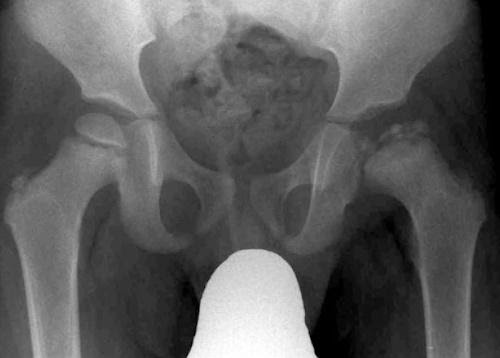

The mechanism of injury involved a forceful football kick, placing rectus femoris under high load, leading to avulsion of AIIS (figures 10 and 11).

Figure 10 – AP pelvic x-ray

Figure 11- Ultrasound AIIS

Progressive heterotopic calcification of the displaced apophysis and scar (subsequently demonstrated on CT scan), led to subspinous hip impingement and marked loss of sporting function and range of movement.